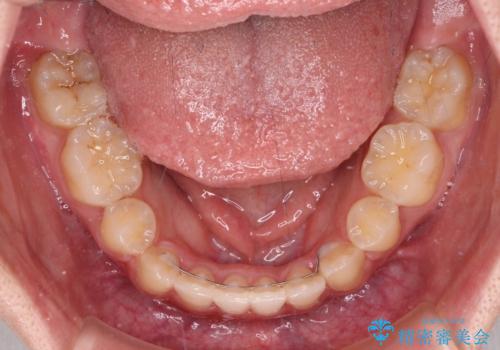

著しい八重歯が気になる インビザラインでの矯正治療

インビザラインでの治療を希望されましたが、インビザライン単独では困難と判断されたため、補助装置や一部ワイヤー装置を用いて行うこととしました。

叢生が強いため、上下左右第一小臼歯4本を抜歯することとしました。

ワイヤー装置を用いた場合、一般的には2年程度で終了することを考えると、「移動量が多くなると治療期間が長くなる」というインビザライン矯正の最大の弱点が現れた治療となりました。